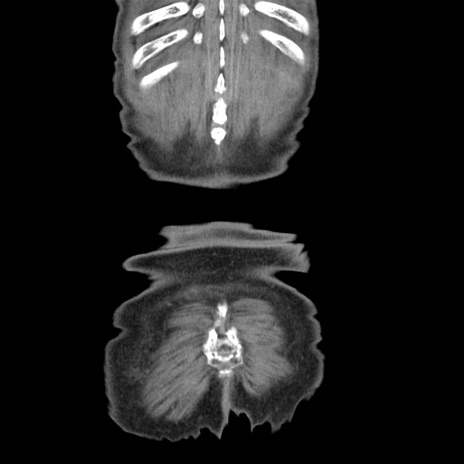

矢状断像